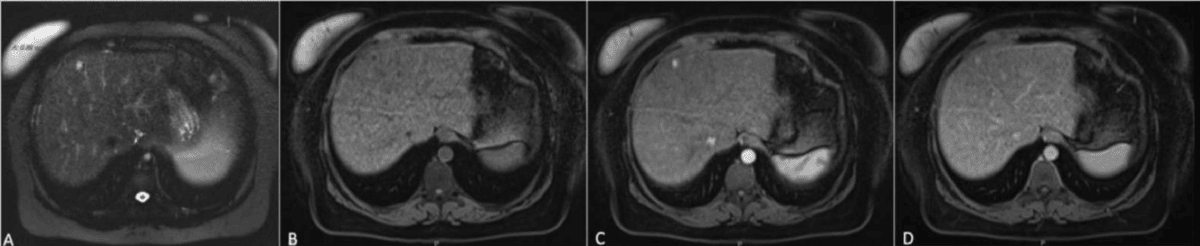

MRI can identify HCCs using a highly specific combination of features, known as the “triple sign”. These include arterial phase hyper-enhancement, wash-out, and capsule appearance40,41. The presence of all three findings strongly suggests HCC, especially in patients with cirrhosis or chronic liver disease.

When hepatobiliary contrast agents are used, healthy liver tissue takes up contrast and appears bright in the hepatobiliary phase, while malignant lesions, lacking functioning hepatocytes, remain dark. This finding is especially useful for identifying small (<1 cm) HCCs and distinguishing them from benign nodules or regenerative tissue. Lesions such as HCC or metastases are typically hypointense compared to the glowing background of the normal liver42–44.